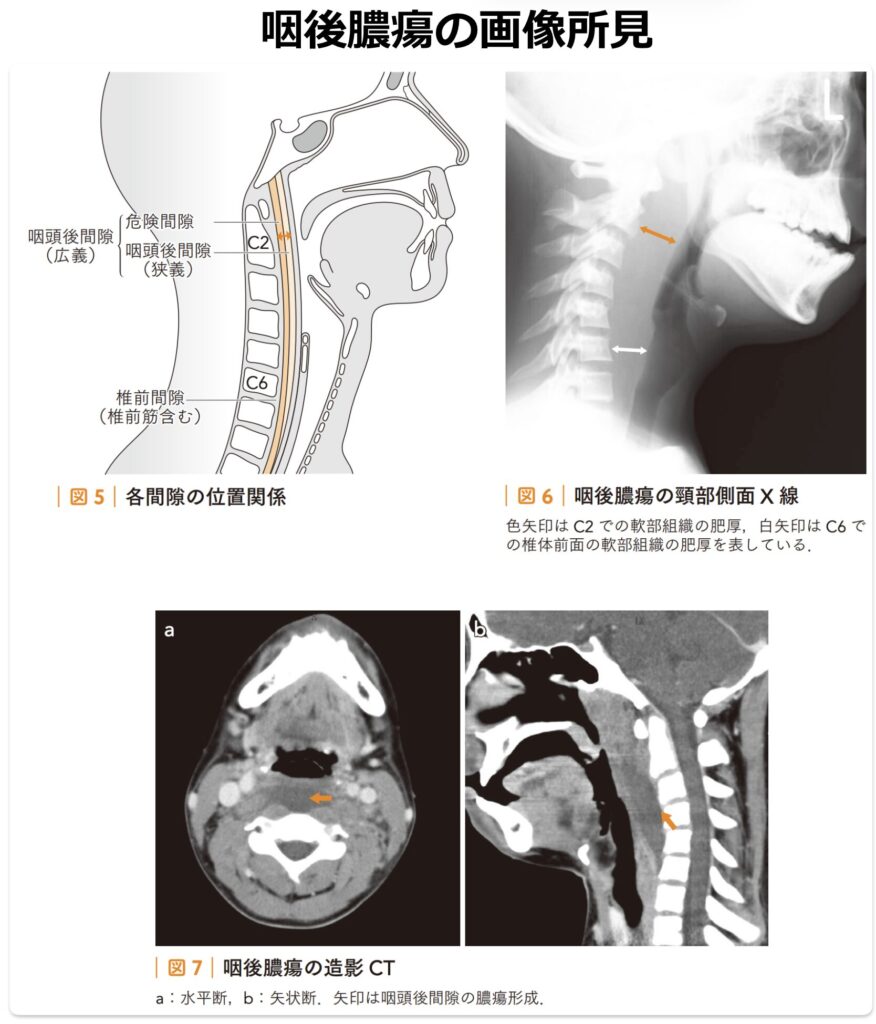

咽後膿瘍 (Retropharyngeal Abscess)

咽頭後壁と頸椎前面との間に位置する咽頭後間隙のリンパ節(咽頭後リンパ節)に膿瘍を形成する深頸部感染症です。

【画像診断】

- 頸部側面X線:可能な限り頸部を伸展させ、吸気時に撮影します。

- 頸椎前面から咽頭粘膜までの距離が、C2レベルで7mm以上、C6レベルで14mm(成人では22mm)以上に膨隆している場合、膿瘍の存在を疑います。

- 頸部造影CT:咽頭後間隙に、辺縁に造影効果を伴う明瞭な低吸収域を認めます。初期症状からは急性喉頭蓋炎との鑑別が困難なことがあるため、鑑別診断および病変の波及範囲の評価として積極的に造影CTを実施します。